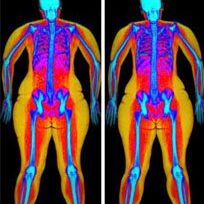

Bodyscan-scaled

Whole body scans to analyze body composition, often used for health weight loss. These scans are uncovered by insurance.